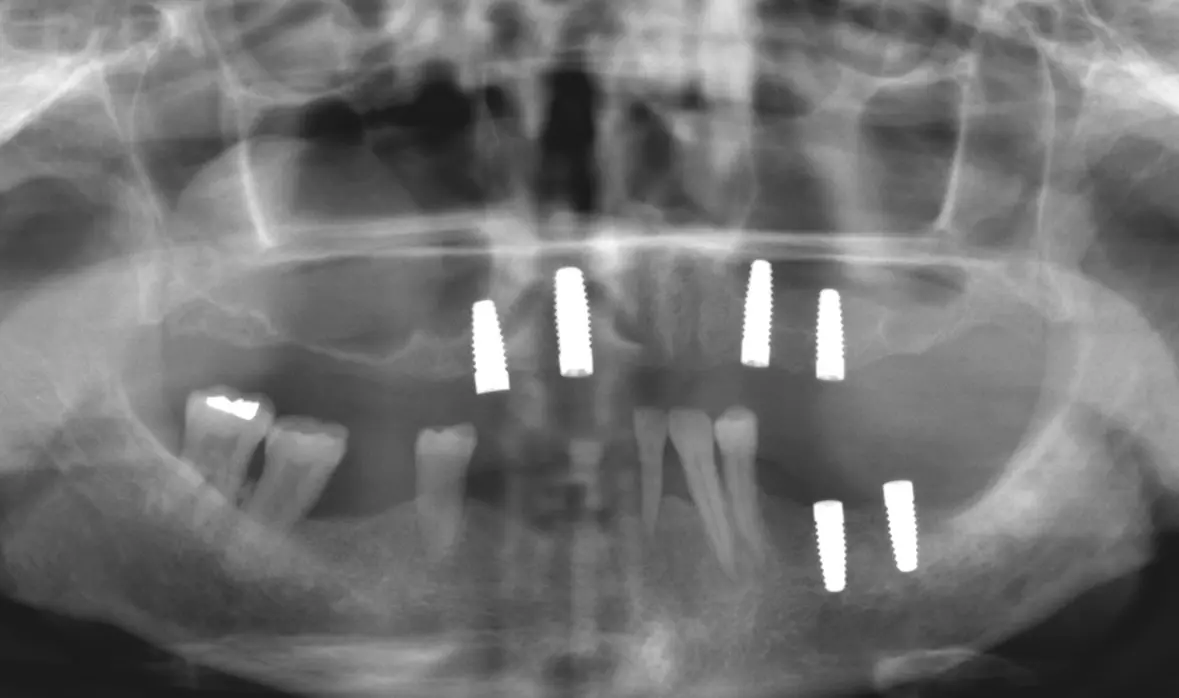

Abb. 2: Nach Implantation im Oberkiefer. Dr. Michael Leistner

Abb. 2: Nach Implantation im Oberkiefer.

Abb. 3: Nach Implantation im Unterkiefer. Dr. Michael Leistner

Abb. 3: Nach Implantation im Unterkiefer.

Die Knochensituation im Oberkiefer war ausreichend für 4 Implantate zwischen 13 und 23 (2 x Zeramex XT 4,2/10 mm und 2 x 4,2/12 mm). Die Freiendsituation im Unterkiefer wurde mit 2 Implantaten im 3. Quadranten gelöst (2 x Zeramex XT 4,2/10 mm). Für den restlichen Unterkiefer war eine festsitzende Brücke von 34, 33, 32, 44, 46 auf 47 geplant. Da neu und seit diesem Zeitpunkt verfügbar, kamen verschraubte Docklocs® Zirkon Abutments aus Zirkonkeramik zum Einsatz.